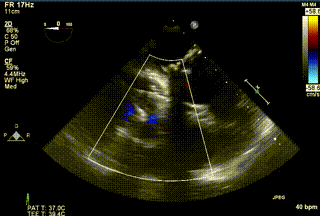

2021年12月24日,復(fù)旦大學(xué)附屬中山醫(yī)院葛均波院士團(tuán)隊成功應(yīng)用LuX-Valve Plus為一例極重度三尖瓣反流(TR)合并房顫、房缺的患者完成了經(jīng)血管三尖瓣置換術(shù),這是在前基礎(chǔ)上,本周完成的第三例經(jīng)血管三尖瓣置換手術(shù),葛均波院士、周達(dá)新教授等與心外科魏來教授、賴顥教授,心超室的潘翠珍教授、李偉教授及麻醉科的郭克芳教授共同完成了本周手術(shù),均獲得圓滿成功!患者術(shù)后超聲顯示無TR,臨床癥狀明顯改善。本周手術(shù)的成功也為LuX-Valve Plus救治性臨床研究添上了濃墨重彩的一筆。

三例患者入院后,葛均波院士團(tuán)隊周達(dá)新教授、潘文志教授、張源博士、陳莎莎博士及心超室的潘翠珍教授、李偉教授對患者的情況進(jìn)行詳細(xì)評估和討論,最終決定為三例患者選擇LuX-Valve Plus40mm、50mm和50mm型號的瓣膜進(jìn)行手術(shù)治療。手術(shù)后即刻拔除氣管插管,術(shù)后患者三尖瓣反流癥狀得到顯著改善,復(fù)查心超結(jié)果顯示人工三尖瓣瓣膜支架固定穩(wěn)定,瓣葉關(guān)閉形態(tài)未見異常,未見明顯反流。